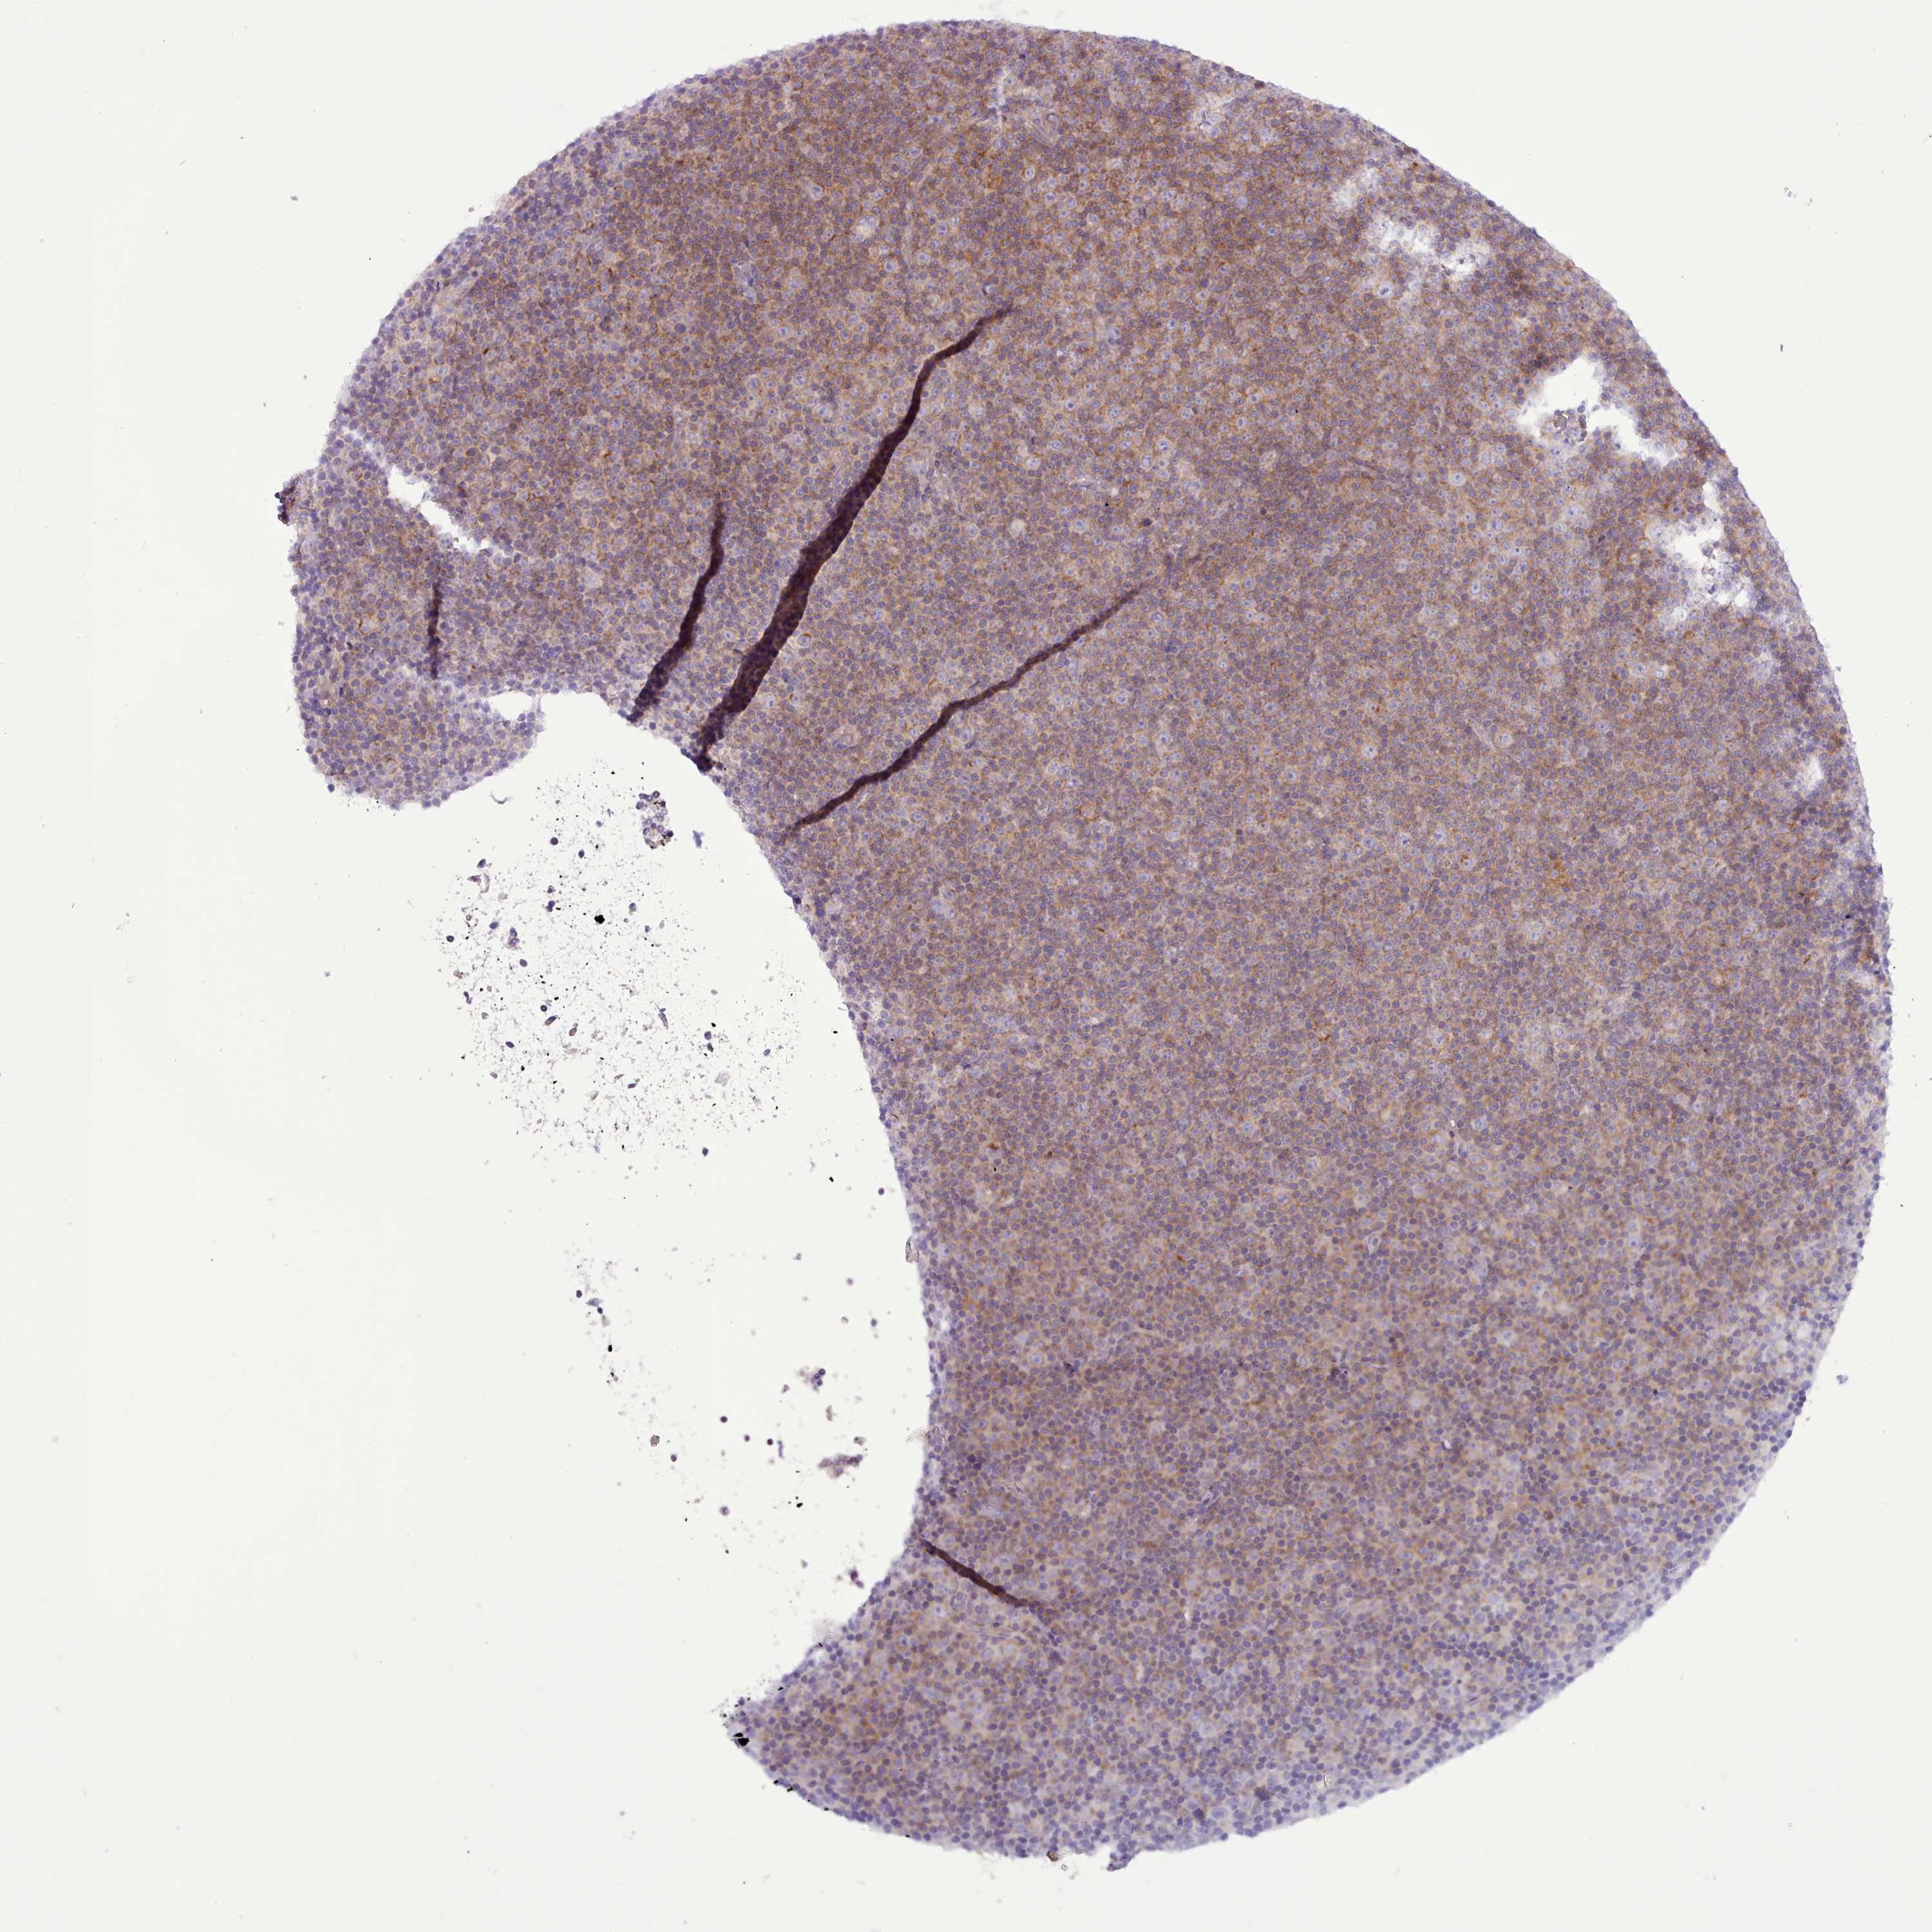

CANCER LYMPHOMA Show tissue menu

LYMPHOMA - Protein expressioni

A mouse-over function shows sample information and annotation data. Click on an image to view it in a full screen mode. Samples can be filtered based on level of antibody staining by selecting one or several of the following categories: high, medium, low and not detected. The assay and annotation is described here.

Each image is clickable and will lead to virtual microscopy that enables deeper exploration of all samples and also displays staining intensity scores, fraction scores and subcellular localization as well as patient and tissue information for each sample.

Antibody HPA042968

Antibody HPA048225

Hodgkin's disease, NOS

Malignant lymphoma, non-Hodgkin's type, High grade

Malignant lymphoma, non-Hodgkin's type, Low grade